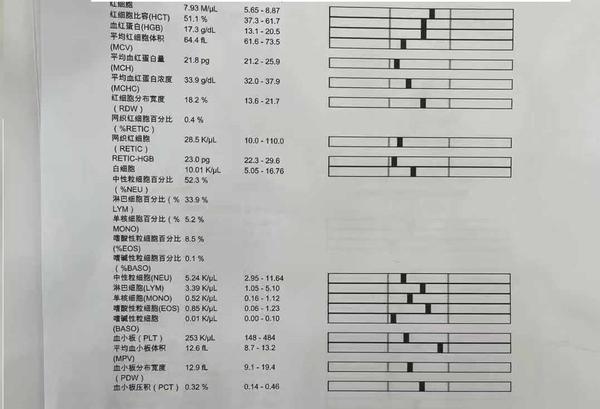

过去半年主人带狗做过多次生化,血常规、粪便检查,有的医院说肠胃菌落失调,有的没有结果。我们经过对化验单的分析,和症状表现按出血型肠胃炎(不是肠胃炎出血)治疗,治疗后最近都没有拉血表现 ,但是14-15天一次的呕吐还是无法找到原因。另外出血型肠胃炎是很少见的疾病,成因目前医学上还未知,根据分析我们认为最大可能是在胃部,担心会出现肿瘤或者未来有溃疡引起的穿孔,所以我们说服宠物主人给狗在当地比较好的医院做一次胃镜确定问题出在那里,在北京大概1000元所以我们认为费用在可以接受范围里。

到医院后医院没有仔细看资料,开了7个检查“生化、血常规、4张X光、1组B超、胰腺炎测试、C反、粪便化验”,就是不肯做胃镜检查。宠物主人不好意思反对医生的意见所以7个化验花了2000元。化验结果和我们预料的一样,每一个都没有问题,甚至可以说狗的身体结果是完美的,血常规和生化里没有任何一项指标高或者低(健康狗里都很少),其中2张片子还是照心脏的。